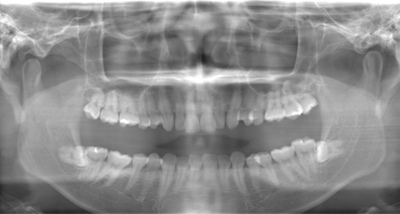

CASE 2

| 年齢・性別 | 30代・男性 |

| 主訴 | 左上下親知らず抜きたい |

| 抜歯期間 | 30分 |

| 抜歯費用 | 約2,500円(保険内) 別途CT撮影で3,000円 |

| 抜歯内容 | 左上下の親知らず抜歯 |

CASE 3

基本情報

| 年齢・性別 | 20代・男性 |

|---|---|

| 主訴 | 左下親知らず抜きたい |

| 親知らずのはえ方 | 半埋伏 |

| 抜歯内容 | 左下の半埋伏親知らず抜歯 |